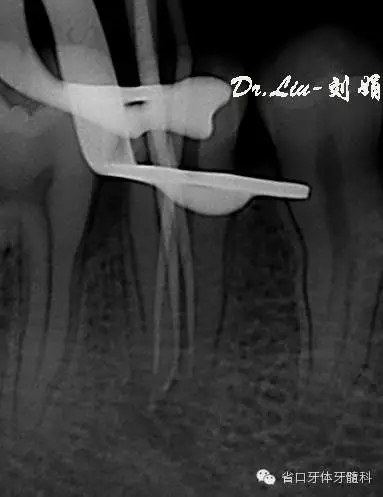

圖5:術(shù)中插尖片,見3根管

根管預(yù)備:顯微鏡下賽特力超聲ETB繼續(xù)去除根管上段及髓腔內(nèi)鈣化物,6#先鋒銼聯(lián)合pathfile銼和超聲逐步通根,測長:L=DB=MB=18mm,WAVE-ONE(Small)備根,紙尖干燥根管,氫氧化鈣糊劑暫封。